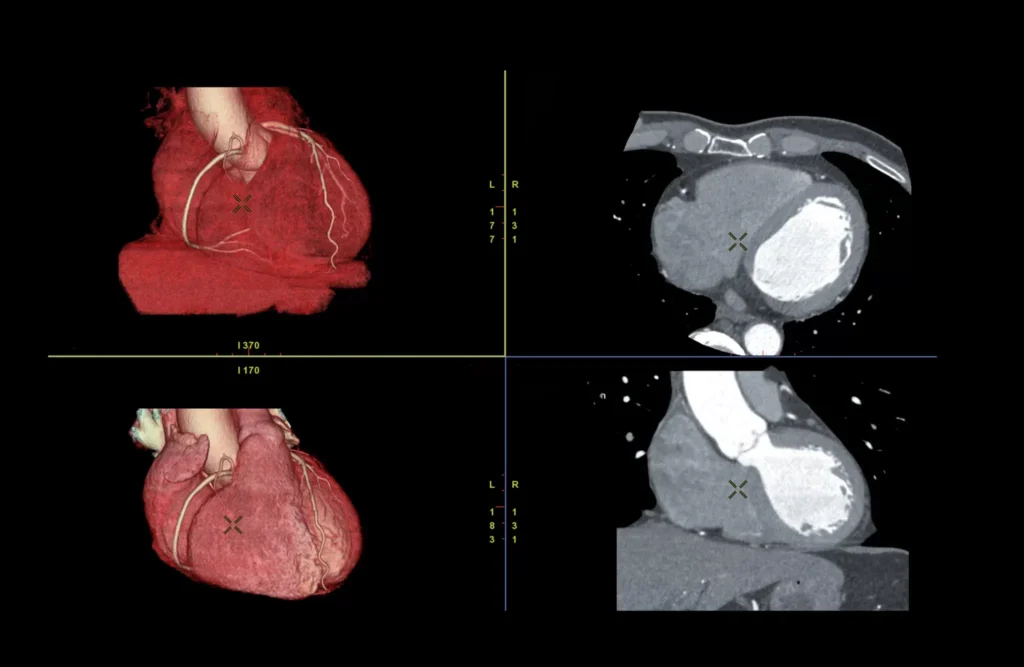

Heart injuries can range from minor bruises to life-threatening tears in the heart muscle. Knowing these common types helps in identifying the injury and getting the right treatment quickly.

This occurs when a strong impact to the chest, such as during a car accident, bruises the heart muscle. It can cause irregular heartbeats and reduced heart function.

This injury happens when an object like a knife or bullet pierces the chest and directly damages the heart tissue. It often requires emergency surgery.

A bruise to the heart muscle caused by trauma, which can lead to swelling, pain, and problems with heart rhythms.

A serious tear in the heart wall, usually following severe trauma or a heart attack. This condition is life-threatening and needs immediate medical attention.